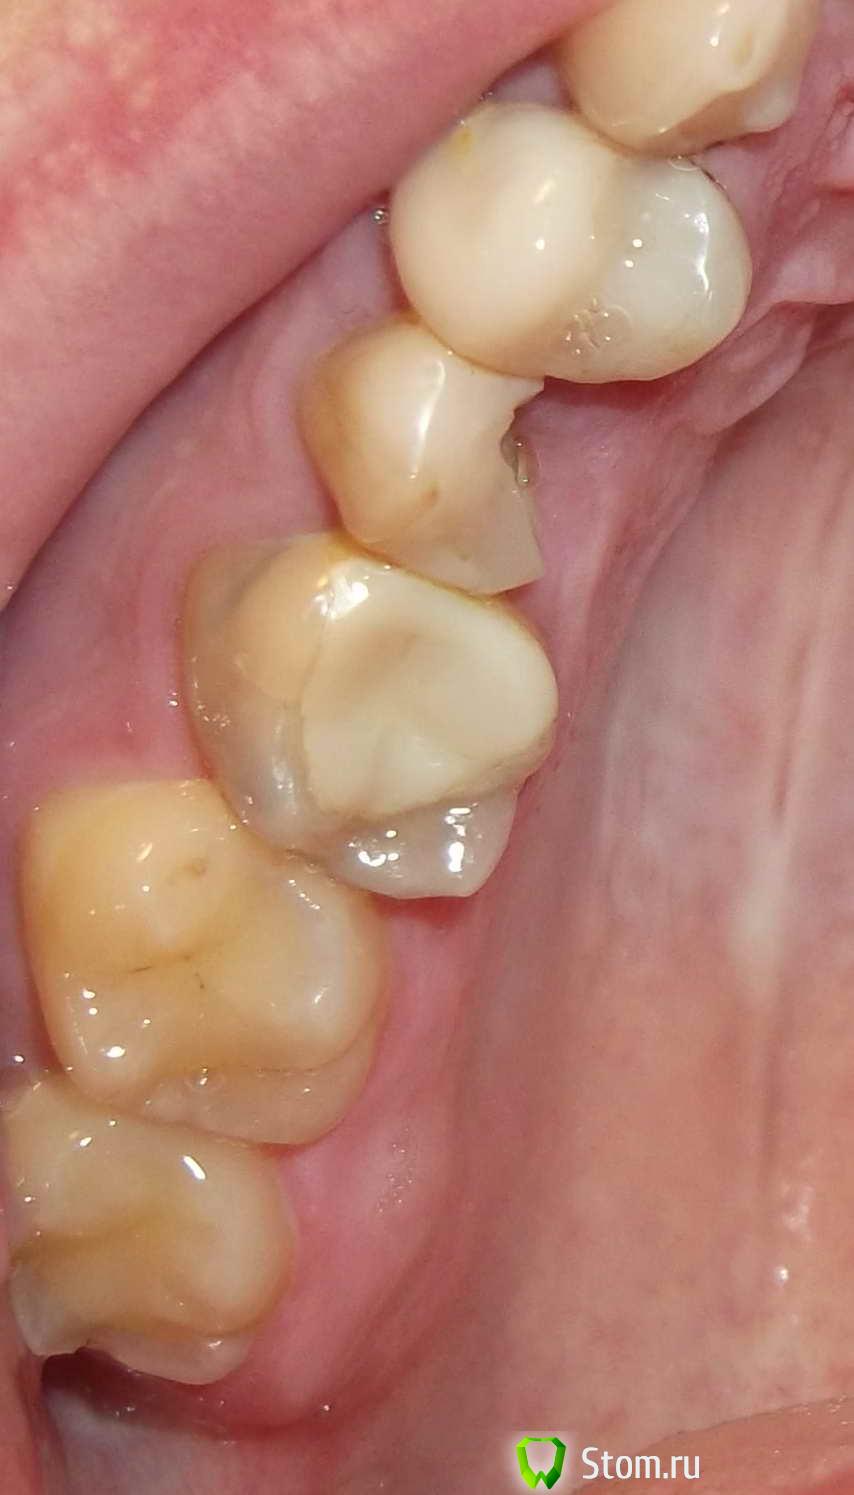

Constantin Опубликовано 30 марта, 2012 Поделиться Опубликовано 30 марта, 2012 Здравствуйте.Нужна консультация по следующему вопросу.Скололась часть пломбы на верхней 5-ке справа.В своё время у этого зуба откололась стенка, скол был под десну.Тогда зуб мне восстановили пломбой и стекловолоконным штифтом.В нынешней ситуации пломбу уже ставить не хотят и отправляют к ортопеду.Был на консультациях в разных клиниках и мнения ортопедов разделились.Первый советует что лучше уже ничего с этм зубом не делать так он дольше прослужит.Второй советует попоробовать поставить пломбу или удалить т.к. коронку ставить не на что,а вкладка в 5-ке плохо держится поэтому он этим заниматься не будет.Третий врач говорит что поскольку в одном канале штифт который вынуть не удасться можно безпроблем поставим вкладку во второй канал и установить коронку. Что посоветуете уважаемые доктора? Спасибо. Ссылка на комментарий

Ст@ся Опубликовано 31 марта, 2012 Поделиться Опубликовано 31 марта, 2012 + к предыдущему мнению.Удаление пломбы, штифта, оценка объема оставшихся тканей.При необходимости - хирургическое удлинение с целью выведения поддесневого дефекта в наддесневой. Затем - перелечивание корневых каналов. Восстановление культевой вкладкой и покрытие коронкой.Если после первого этапа прогноз неблагоприятный - удаление зуба с последующей имплантацией. Ссылка на комментарий